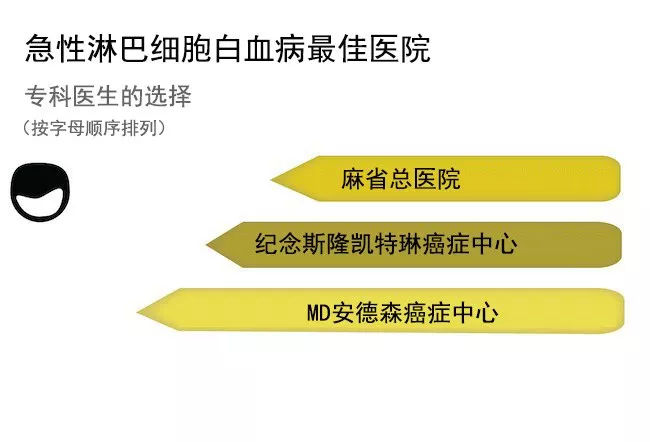

出国看病 美国医生眼中的医院 2018年新排名

出国看病 美国医生眼中的医院 2018年新排名